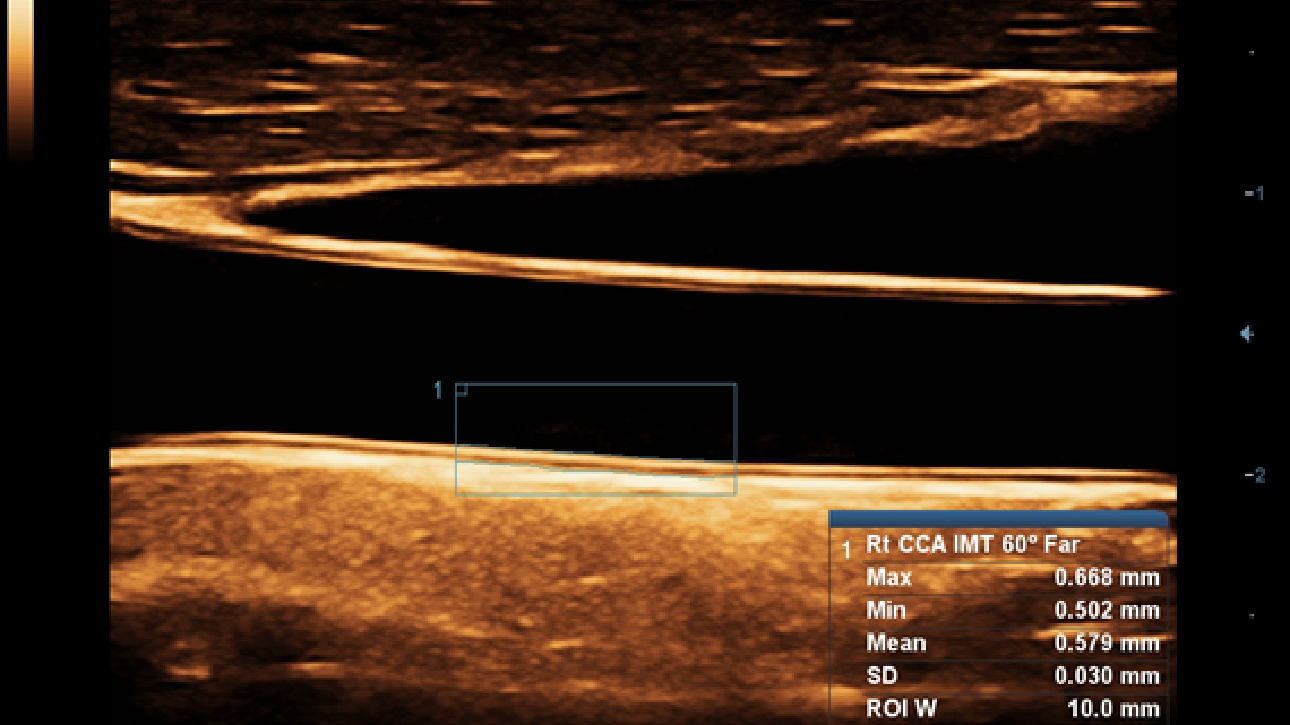

Klinische Bilder